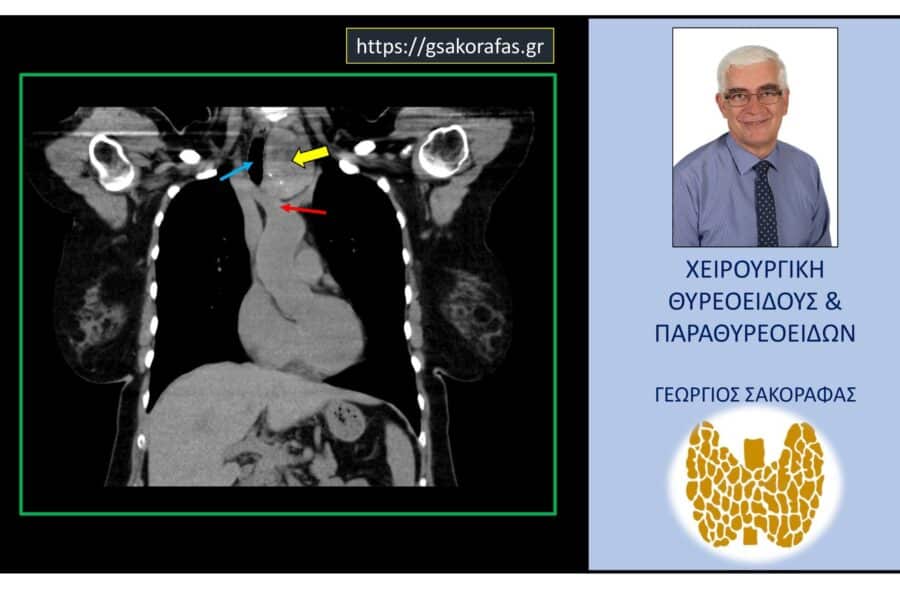

Καταδυόμενη Βρογχοκήλη Ευμεγέθης καταδυόμενη βρογχοκήλη – με αφορμή ασθενή μας (εικόνες) Ευμεγέθης καταδυόμενη βρογχοκήλη – με αφορμή ασθενή μας (εικόνες) Η ασθενής, ετών 60, προσήλθε για…George Sakorafas21 Φεβρουαρίου 2024